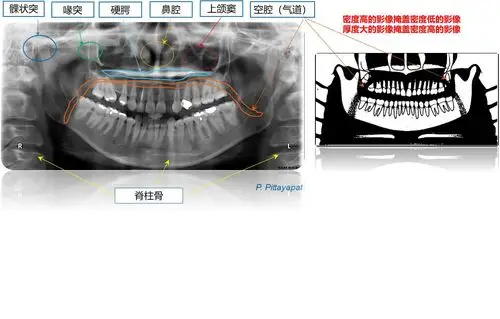

伯爵cbct影像篇③口腔全景片认知

口腔全景片提供的是二维影像,所以它的分辨率不如ct高,而且只能提供一